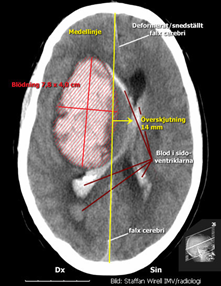

Typ av undersökning? Vad visar bilden?

På akutmottagningen tar neurologjouren emot och bestämmer sig relativt omgående för att göra en akut datortomografi av hjärnan. Under väntetiden blir Hjalmar allt mer motoriskt orolig och oklar. Narkosläkare tillkallas och man tvingas söva och intubera patienten för att kunna genomföra röntgenundersökningen. Neurologjouren meddelas röntgensvaret och tillkallar omgående neurokirurgjouren. Då hon ser patienten på akuten är han sövd men nu är höger pupill större än vänster och de drar endast ihop sig trögt och ytterst lite då man lyser i dem. Patientens puls har börjat sjunka och är nu nere på 40/min. Hon beslutar om utrymning av hematomet och Hjalmar förs omedelbart till operationssalen. Under transporten dit får han intravenöst Mannitol och hyperventileras.